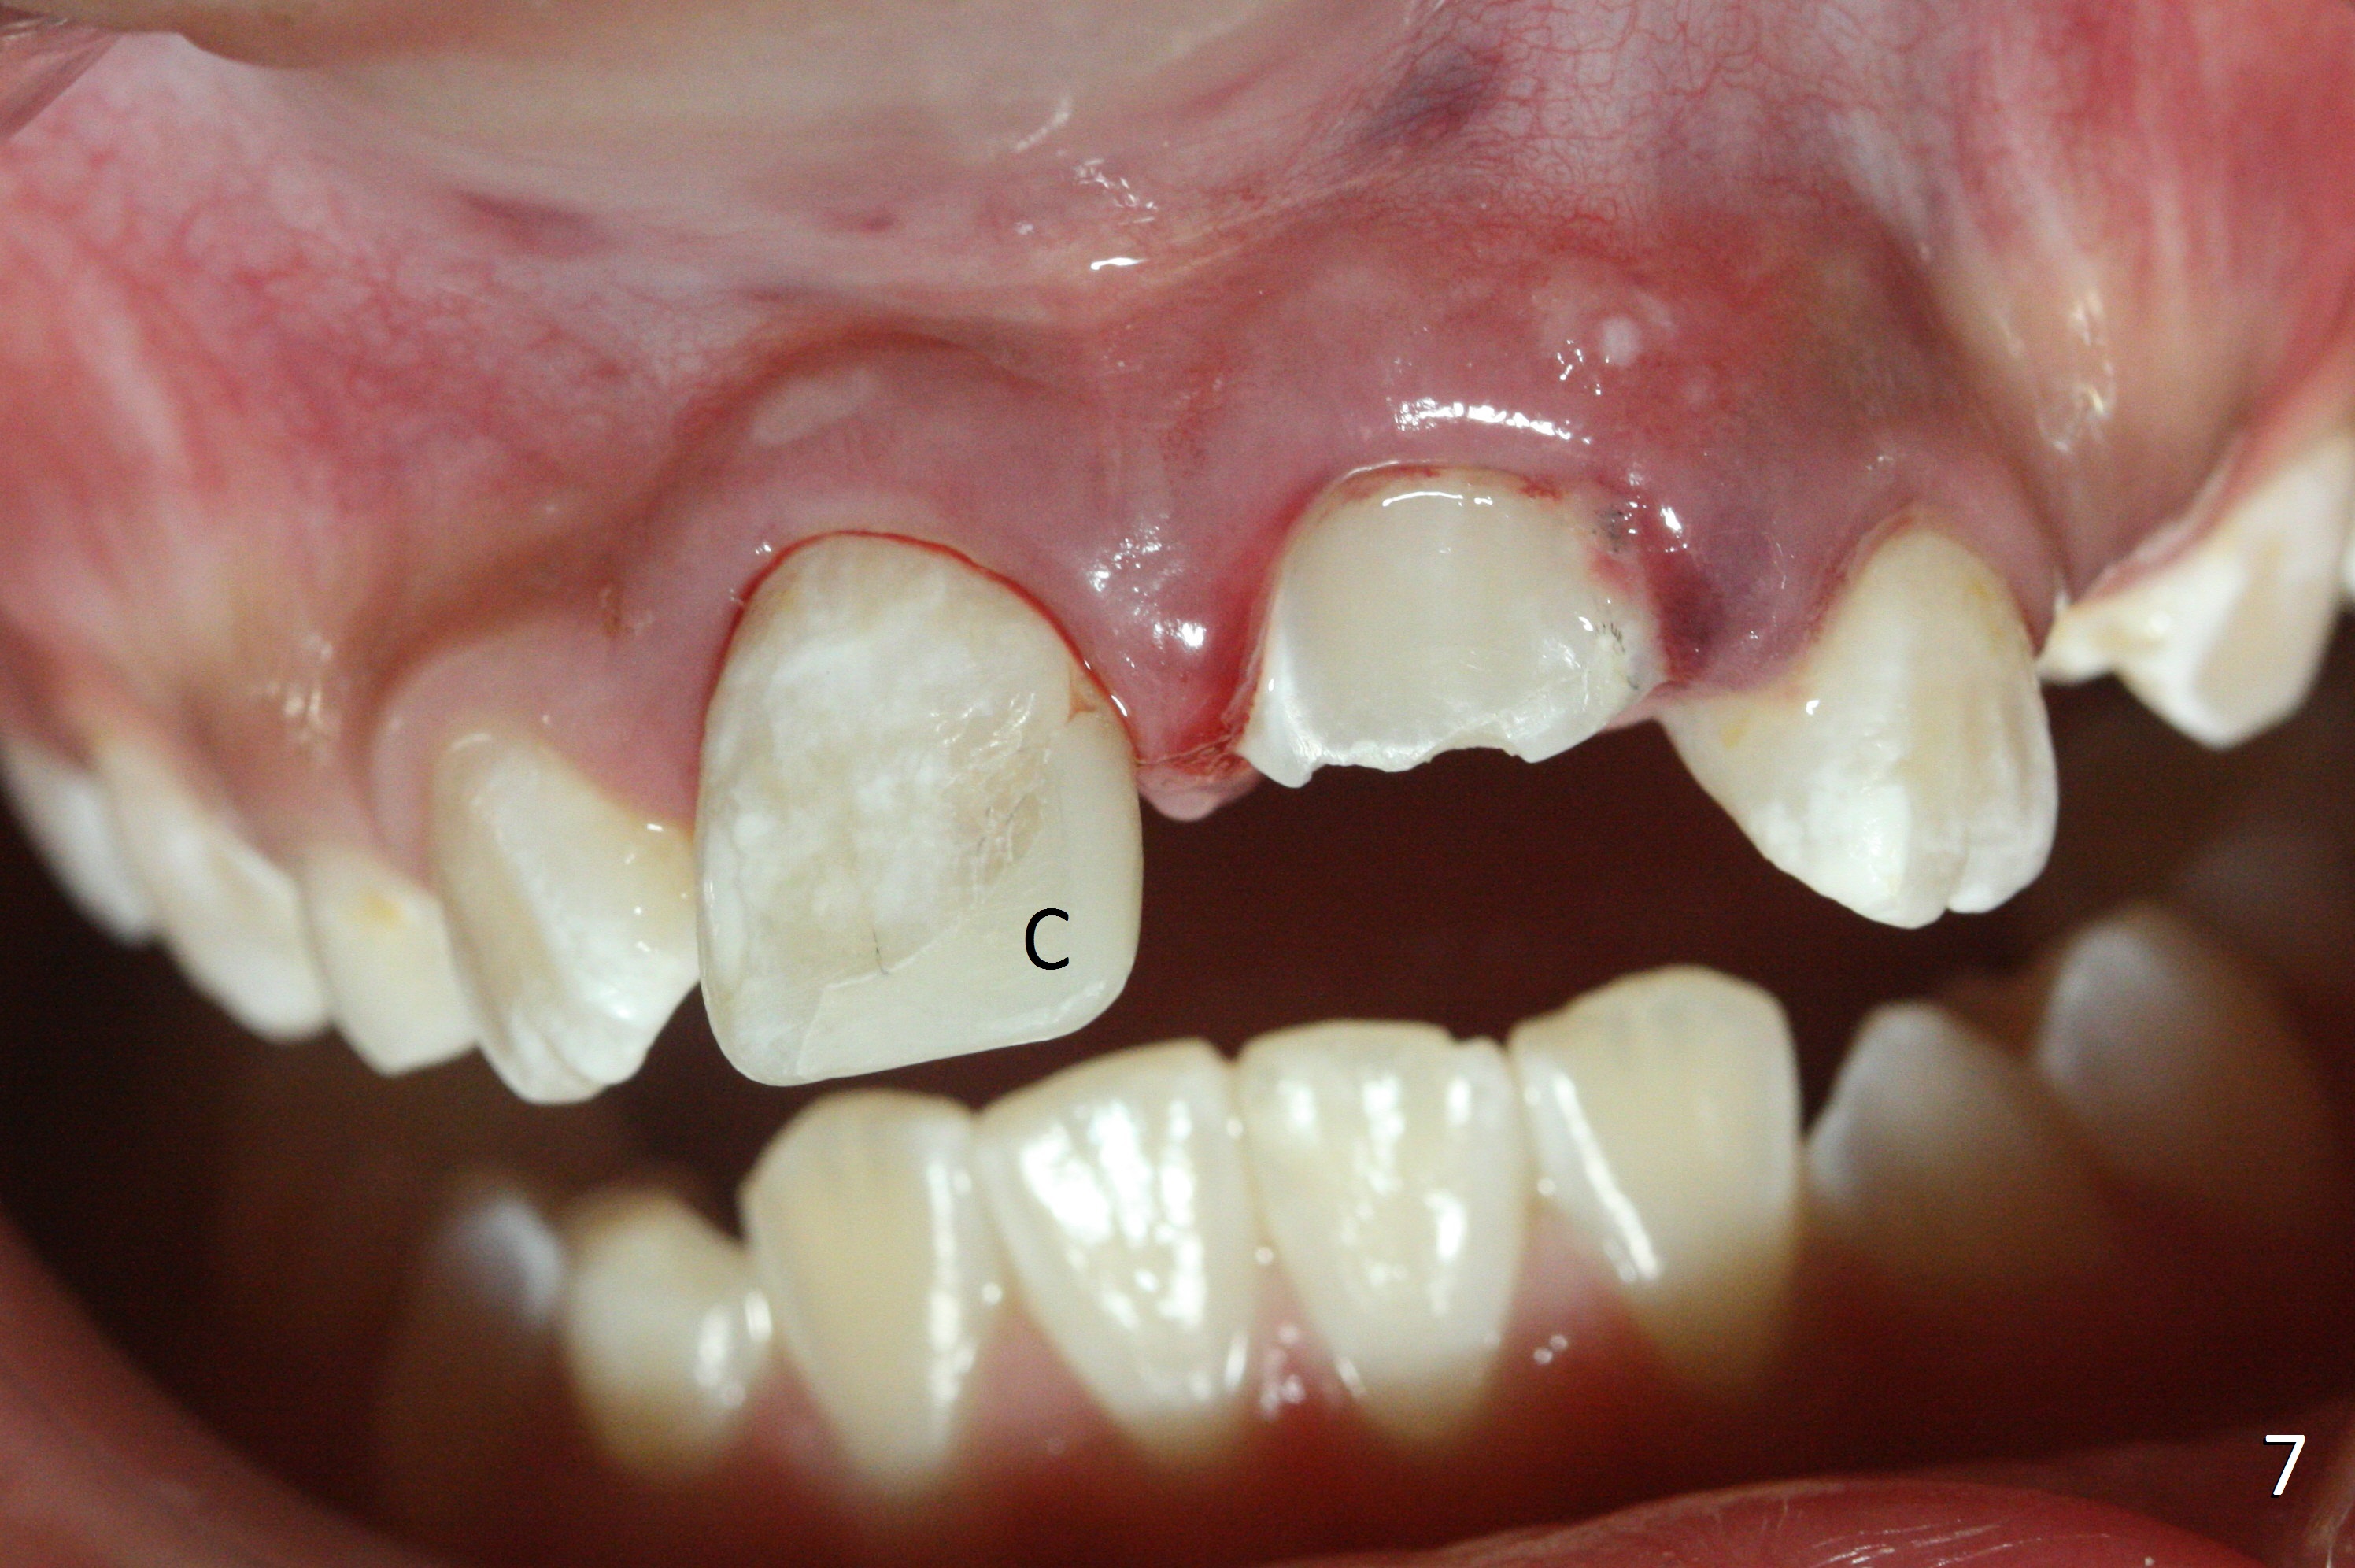

A 10-year-old boy has had Class II Division II malocclusion (Fig.1 impression taken 1 year earlier). He is brought to clinic the 2nd day after a bike accident. The tooth #8 fractures (Fig.2-4) with mesial pulpal horn exposure (Fig.3 *, while #9 intrudes. After debridement of the affected teeth (Fig.5), the exposed pulpal tissue is resected (partial pulpotomy to keep the tooth vital to finish root and apex development) and the pulpal horn is filled by MTA at #8 (Fig.6 *). The tooth #8 is restored with composite (Fig.7 C). Forceps fail to extrude the tooth #9. His parents are reluctant to accept orthodontic extrusion, which is accomplished by Dr. Shaughnessy 2 days later (Fig.8,9). The patient will leave for China in 2 days and will return in a month.